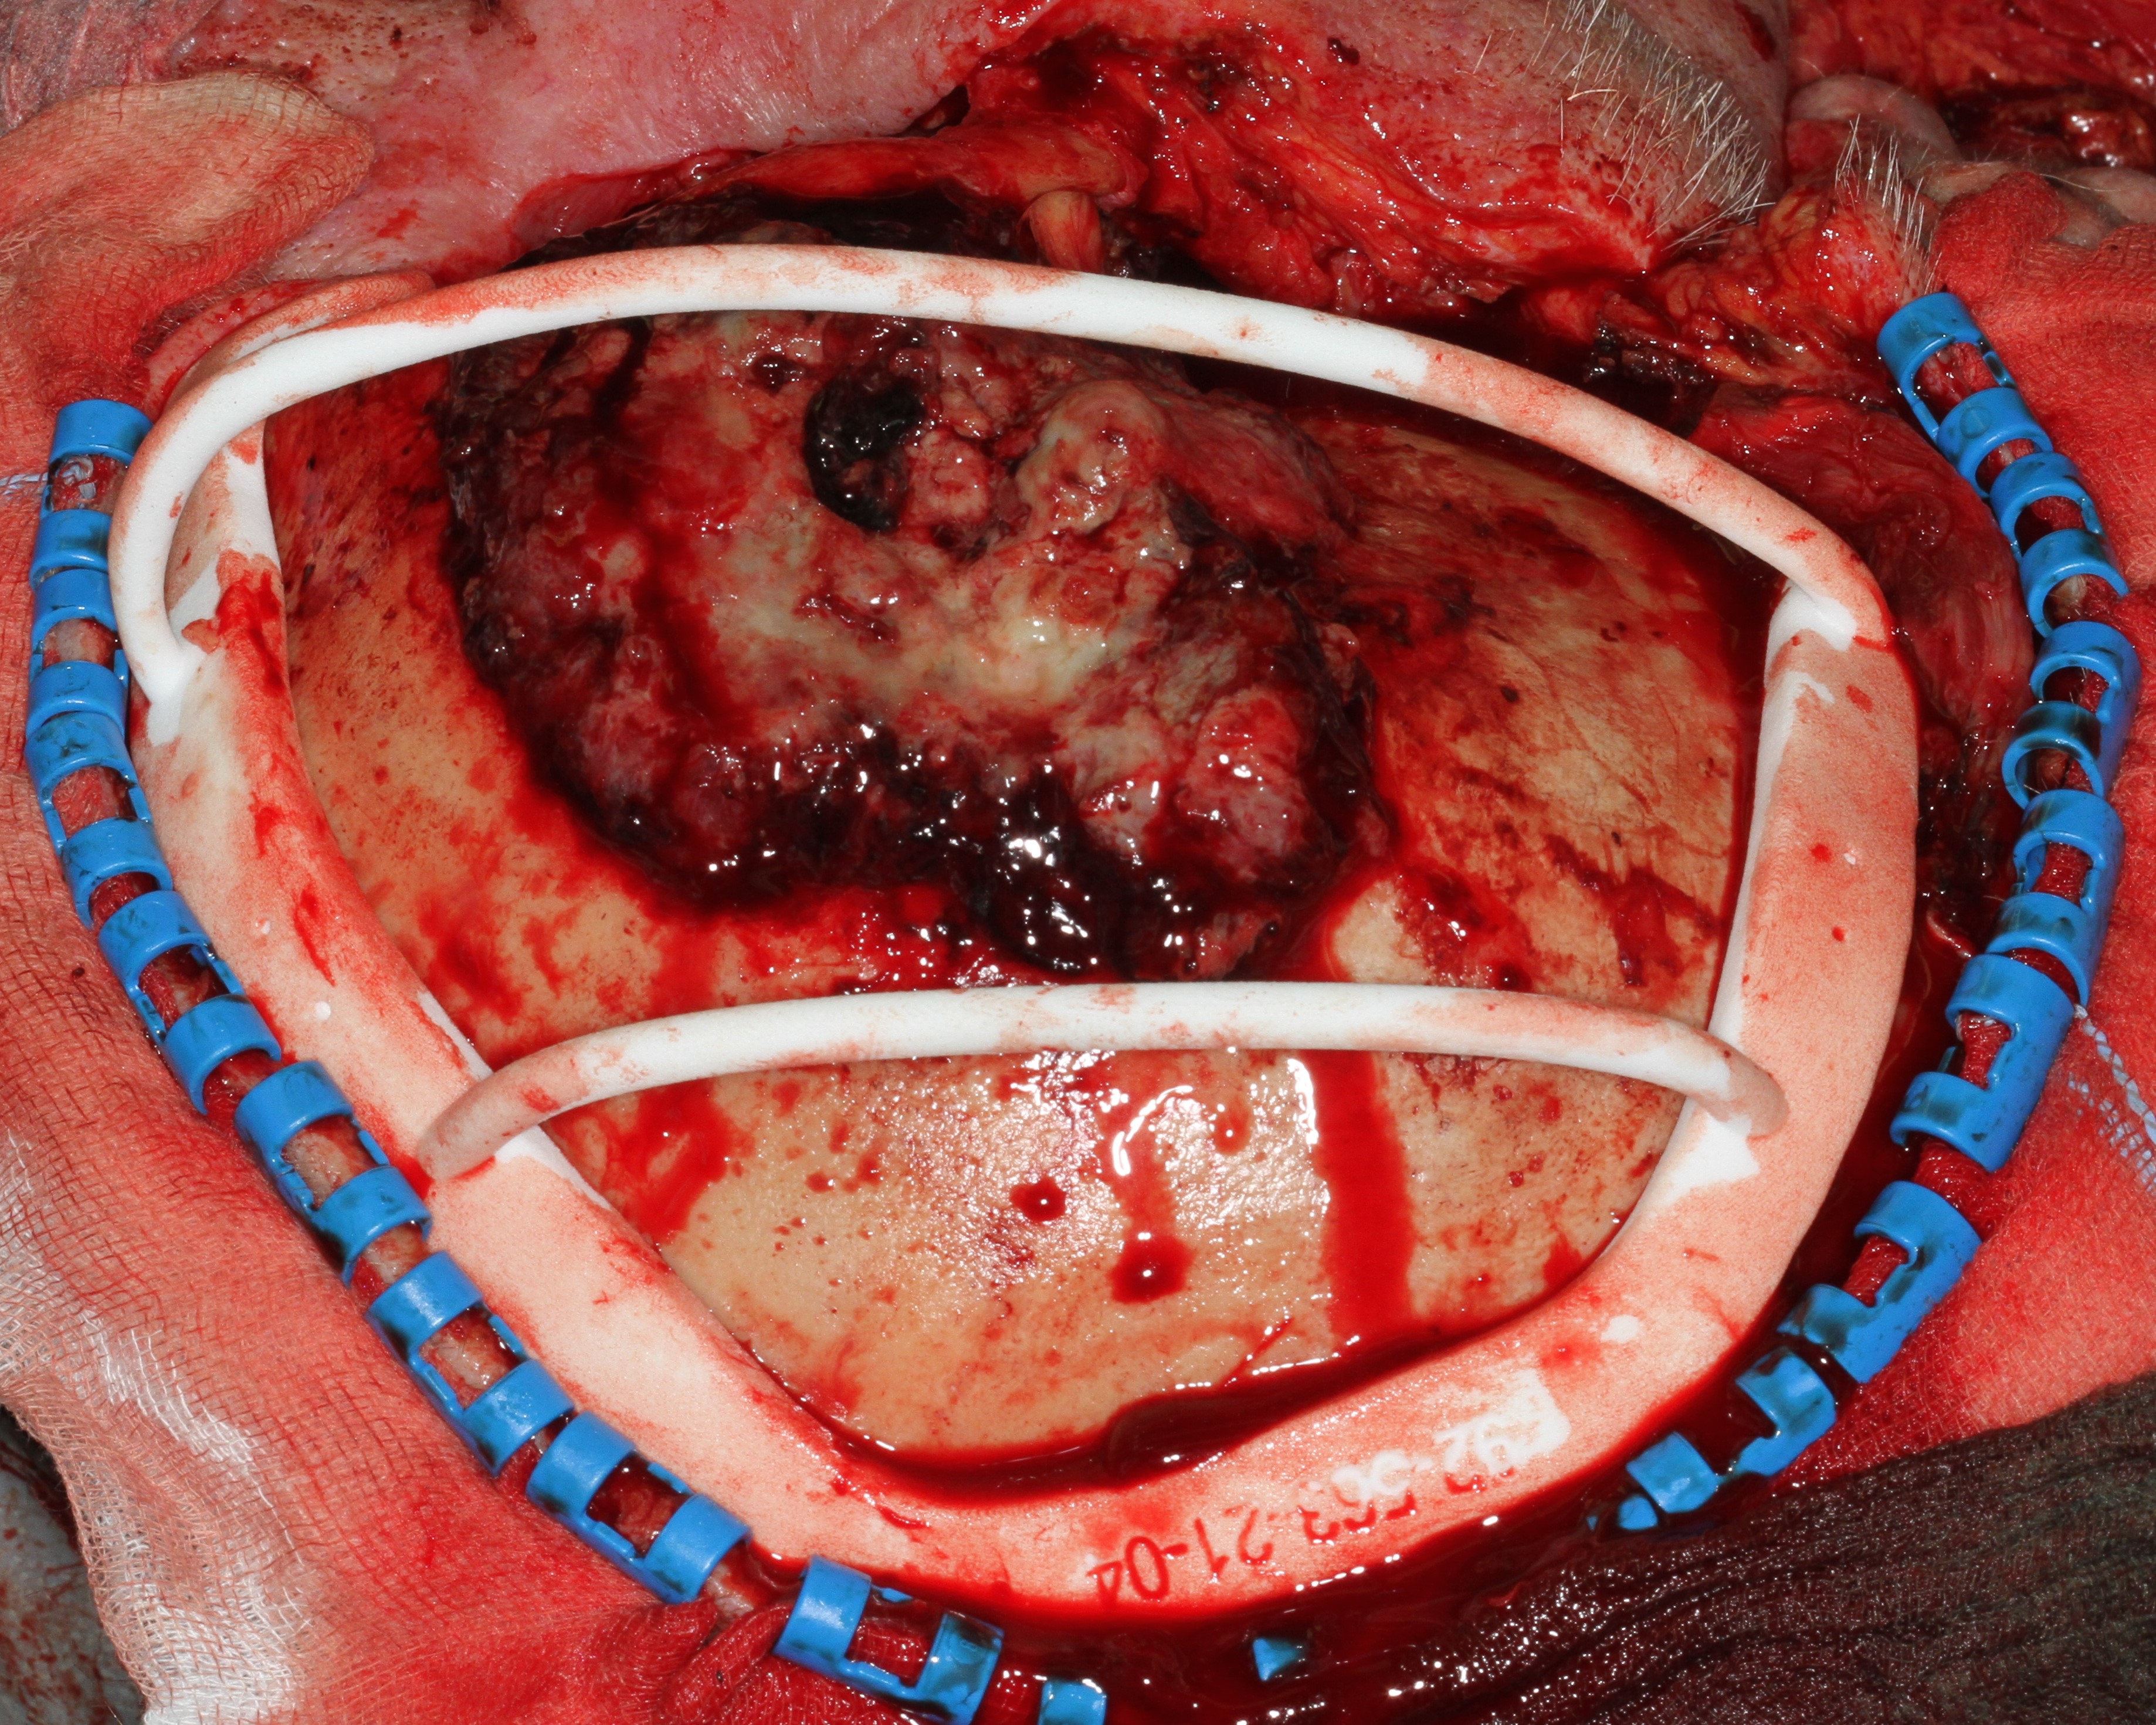

The removal of the affected part of the skull is planned based on a CT scan. To aid precise excision while minimising unnecessary bone loss, a resection guide is 3D printed from the high-resolution CT data. After resection along the resection guide, an implant exactly fitting into the defect is placed to protect the brain (Figure 12).

Figure 12: Cranial implant placed in the defect of the skull and fixed by screws.

At the end of surgery, the skull implant has to be covered by a soft tissue flap to protect the implant from infection. Here the soft tissue coverage is provided by an anterolateral thigh free flap (Figure13).

Figure 13: Cranial implant covered with soft tissue free flap.